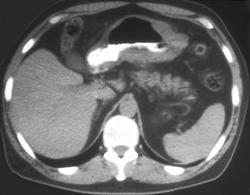

Gastric Volvulus